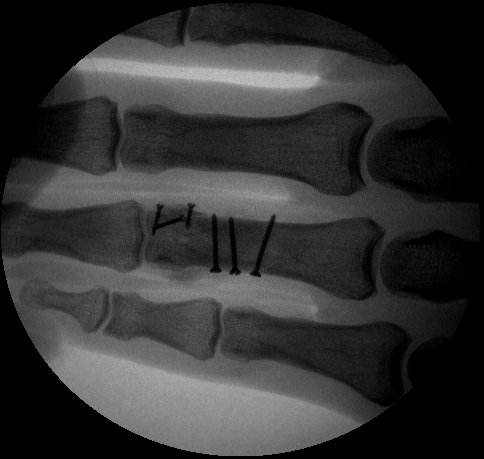

Clinical Example: Proximal phalanx bicondylar oblique volar coronal head fracture

This gentleman sustained a closed severe torsional injury of the right ring finger.

Xrays show a complex intraarticular fracture of the proximal phalanx head. There is a displaced spiral oblique longitudinal fracture with a second oblique coronal split through the articular surface of the radial condyle.

Intraoperative fluoroscopy.